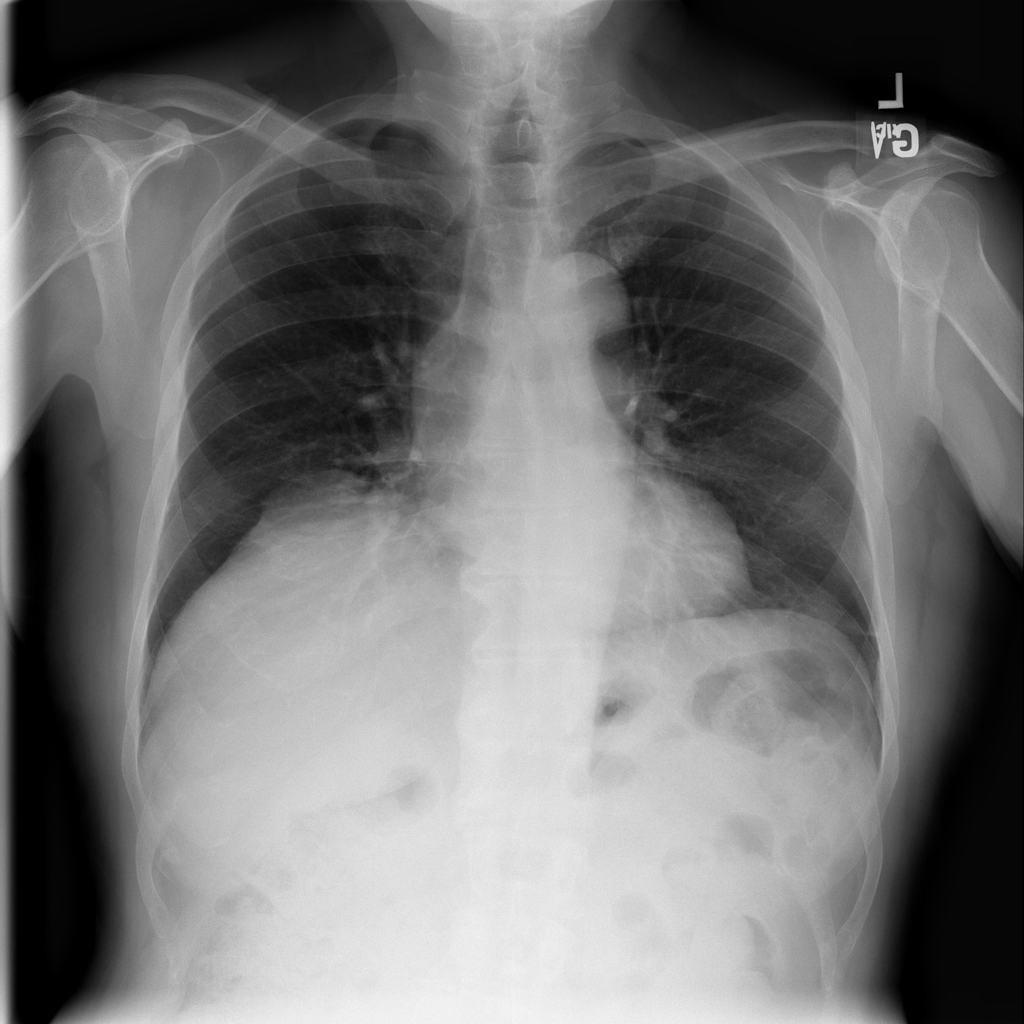

PAT-50E2 · IMG-000Hernia

PAT-50E2 · IMG-000

AP